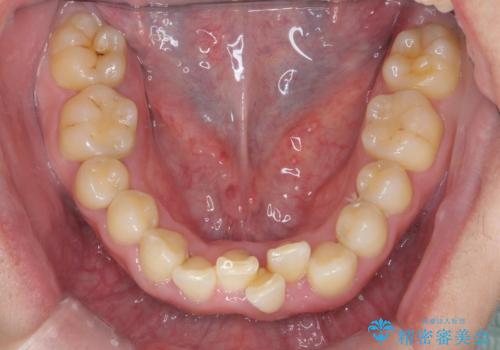

前歯のすき間 歯のがたつき

- 前歯のすき間とがたつきを主訴に来院。

右上の前歯は過去にがたつきがあったとのことで抜いてしまっていました。

歯の数を合わせるために、下の歯を1本抜いて矯正しています。

下の前歯を抜歯したことでブラックトライアングルができましたが、仕上げにIPRを加えることで目立たなくすることができました。